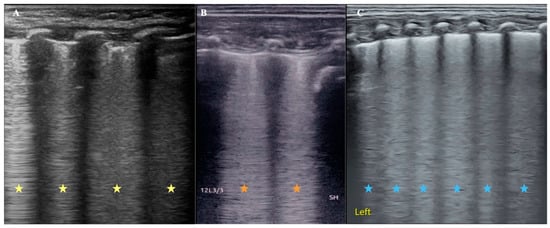

It is well known that viral pneumonia is mainly a kind of interstitial disease, and its pulmonary edema is mainly interstitial edema, while the wet lung of a newborn is mixed pulmonary edema. As mentioned above, we established a rabbit model of alveolar pulmonary edema by instillation of 0.9% NaCl through the endotracheal tube [19,20]. In these cases, severe pulmonary edema of varying nature is found on ultrasonography as confluent B-lines [Figure 1], which can develop into enigmatic B-lines or white lungs. Figure 1 shows that pulmonary edema, whether alveolar, interstitial, or mixed, has the same or similar appearance on ultrasound.

Cardiogenic pulmonary edema can be a life-threatening condition and a common cause of respiratory failure in emergency medicine; both animal experiments and clinical studies have confirmed that LUS can cause cardiogenic pulmonary edema [16,28,29]. Based on pathophysiological mechanisms, cardiogenic pulmonary edema is mainly manifested as interstitial pulmonary edema in the early stage and can further cause alveolar pulmonary edema and mixed pulmonary edema as the disease deteriorates. As mentioned above, pulmonary edema of any property appears as a B-line increasing on the ultrasound image (Figure 1), just the type of B-line varies with the degree of pulmonary edema. Therefore, strictly speaking, LUS cannot distinguish between cardiogenic and pulmonary lung edema. However, since the main cause of cardiogenic pulmonary edema is left heart failure, we can distinguish this using cardiac ultrasound.

Figure 1. Comparison of ultrasound B-line manifestations of pulmonary edema with different properties. (A): An infant with viral pneumonia. LUS appears as confluent B-lines (yellow asterisk). (B): Rabbit model of pulmonary edema. Because LUS examination was performed immediately after 0.9% NaCl was injected into the lung from the endotracheal tube, the kind of pulmonary edema should be mainly alveolar pulmonary edema at this condition, and LUS appeared as confluent B-lines (brick-red asterisk). (C): Infant with wet lung. The mixed pulmonary edema and LUS also showed confluent B-lines. It is difficult to distinguish the type of pulmonary edema from the appearance of the B-lines (blue asterisk).